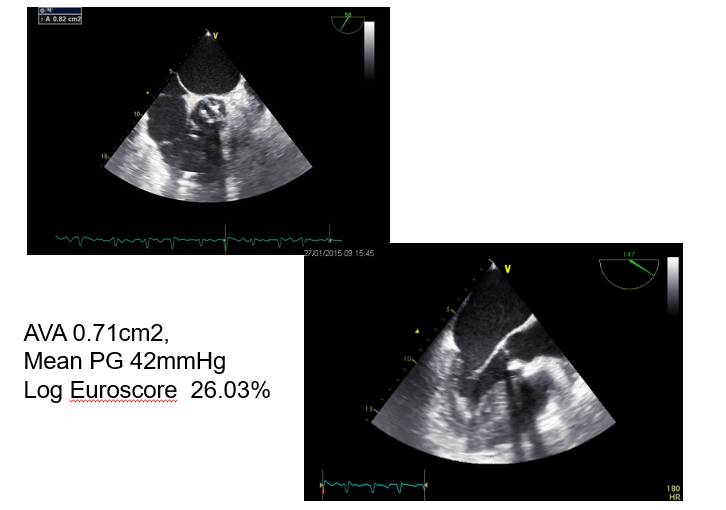

◆患者,男,77岁

◆因“反复胸闷、气喘一年” 2014年12月16日入院

◆患者近一年前劳累后出现胸闷、气喘不适,休息后症状可逐渐缓解,患者就诊于鼓楼医院,TTE示重度AS伴AR

◆建议外科治疗,患者及家属拒绝。

◆予利尿、强心等药物治疗,症状稍好转,但易反复。

◆患者一年来,胸闷、气喘症状反复发作,自感症状逐渐加重,曾数次住院治疗。

入院后治疗

◆静脉西地兰0.4mg IV

◆地高辛0.125mg/d PO

◆华法林2.5mg/d

◆立普妥20mg/d

◆氯吡格雷75mg/d

◆特苏尼2mg/d IV

◆安体舒通20mg/bid

◆症状缓解不明显。

◆仍心率快,呼吸急促。

CAG

◆2014年12月19日于我院行CAG检查:左主干未端至LAD开口80%狭窄;RCA近段60%狭窄。

◆于一周后行冠脉介入治疗,于左主干跨前降支近段植入3.5x36mm支架。

◆术后症状有所缓解,但仍有反复心衰发作。

主动脉及瓣膜CTA

◆Annulus (mm)

◆Min 24.3mm

◆Max 28.3mm

◆Mean 26.3mm

◆Perimeter 82.5mm

THV 29mm

◆2015年1月17日行TAVI术。

◆植入29mm CoreValve人工支架瓣膜一枚。

术后症状明显缓解,近一年未因心衰住院;

一年期复查心超,未见主动脉瓣狭窄和关闭不全。